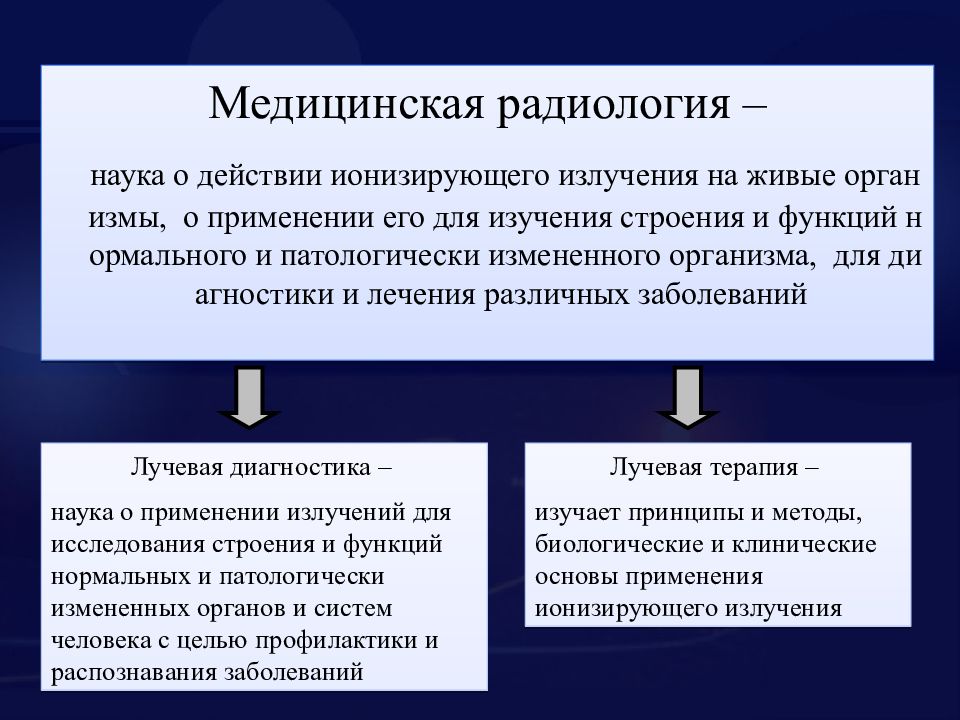

Радиология и радиотерапия? В чём разница. Ядерная медицина и лучевая терапия.